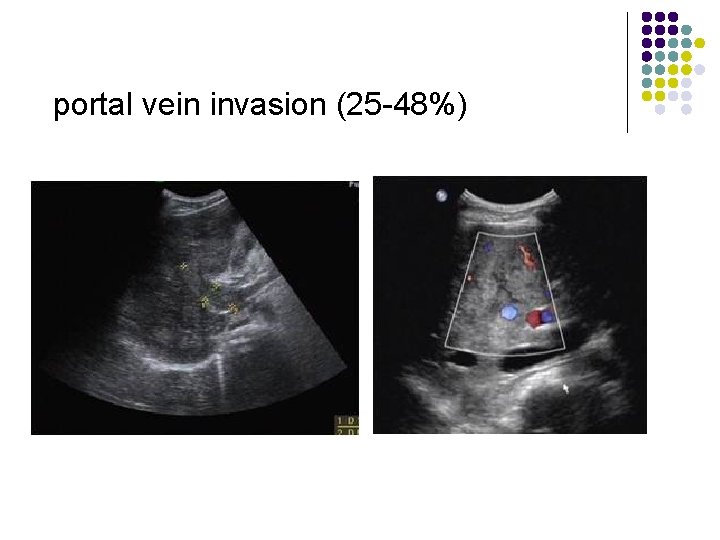

HCC l l l l Metastases to: lung (most common = 8%), adrenal, lymph nodes, bone portal vein invasion (25 -48%) arterioportal shunting (4 -63%) invasion of hepatic vein (16%)/IVC (= Budd-Chiari syndrome) occasionally invasion of bile ducts calcifications in ordinary HCC (2 -25%); however, common in fibrolamellar (30 -40%) and sclerosing HCC hepatomegaly and ascites tumor fatty metamorphosis (2 -17%)

portal vein invasion (25 -48%)